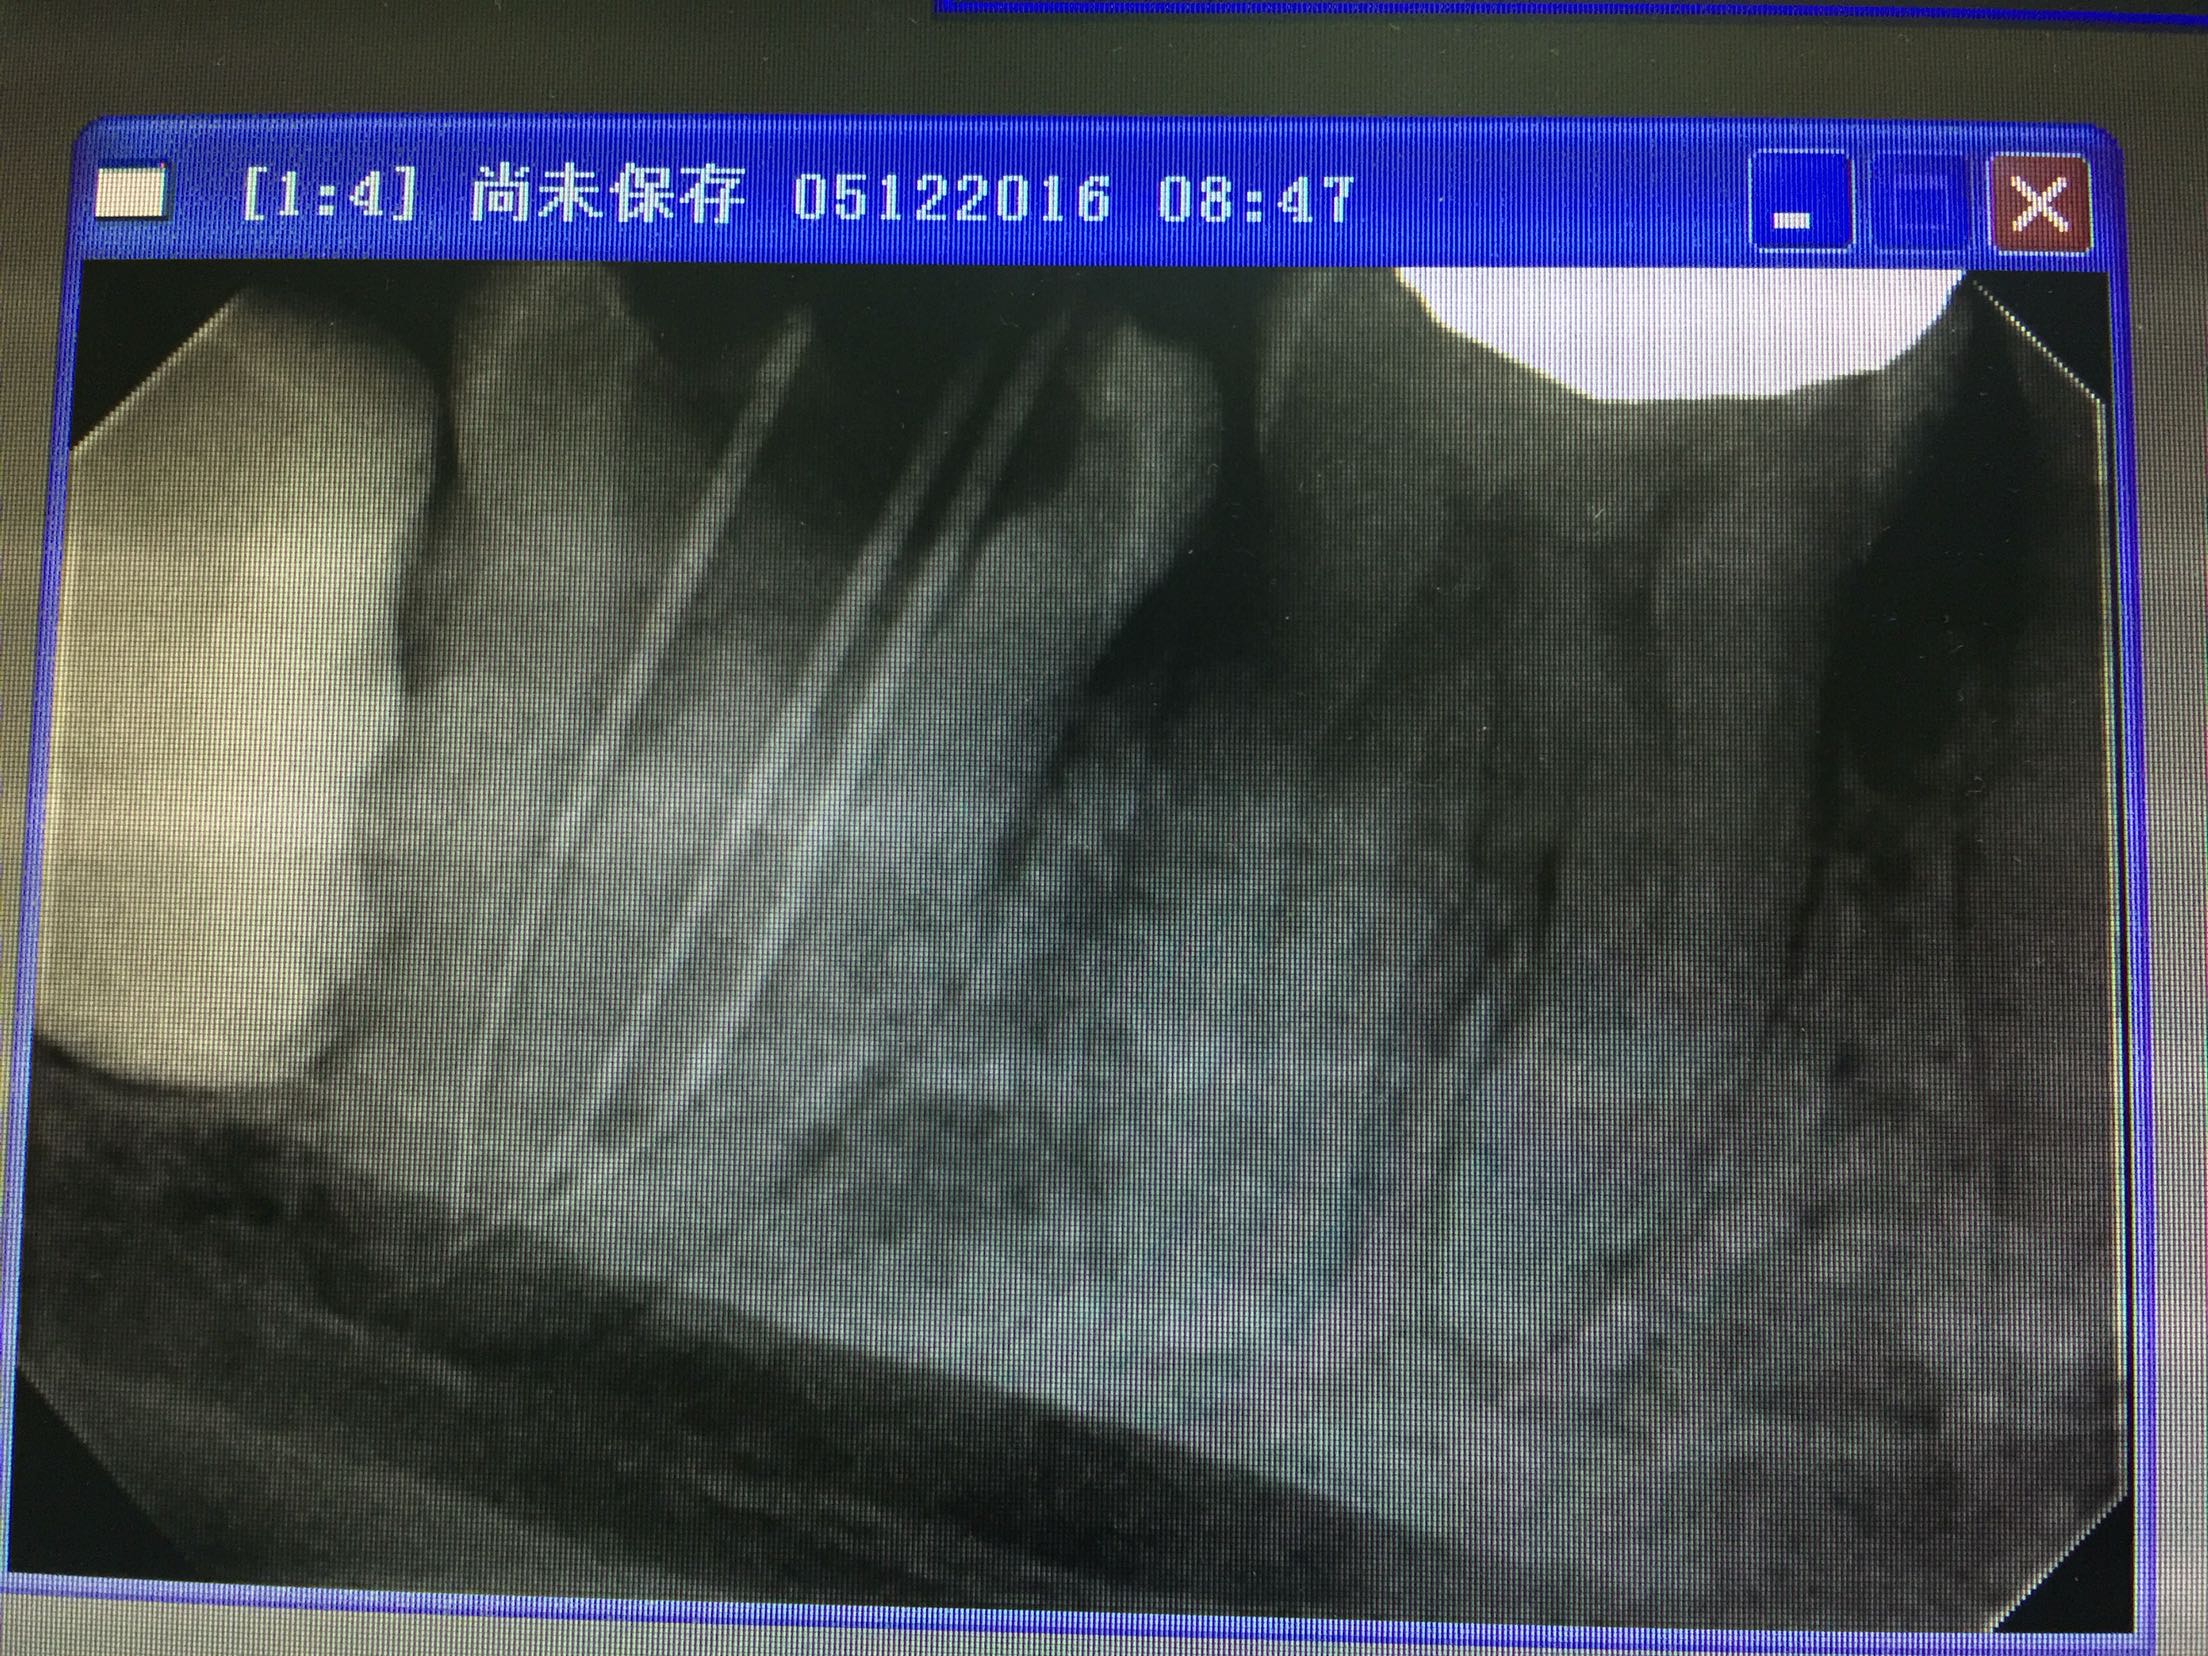

检查:47颊合面深龋,探及穿髓点,探诊(+),叩诊(+-),松动不明显,牙龈无明显红肿,冷诊(++)。辅查:47合面低密度影像及髓。

诊断:47牙髓炎 治疗:47局麻下去龋净,开髓揭顶全,拔髓,疏通根管,根管中上段预备,长度测量,waveone根管预备,1%次氯酸钠冲洗,试尖,干燥,根管封药,告医嘱,肿痛随诊? 复诊无不适。47去暂封及根管封药,终末冲洗,干燥,根充,适充,锌基,树脂充填,调合,抛光,告医嘱,建议择期冠修复。